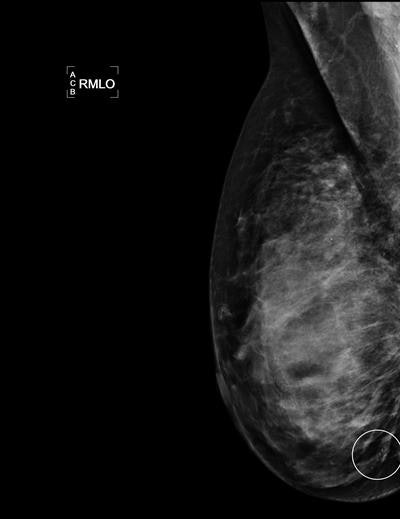

Radiologists interpreting mammograms demonstrated a wide range of sensitivity for detecting cancer, according to results of a study published July 28 in Radiology. The authors believe the findings justify the use of computer-aided detection (CAD) solutions for breast screening.

Tabár, who was not involved in the research, cited stellate/spiculated cancers and microcalcifications as being among those detected with a higher sensitivity, while circular/oval-shaped cancers as well as architectural distortion are, although often fast-growing, aggressive cancers, frequently missed.